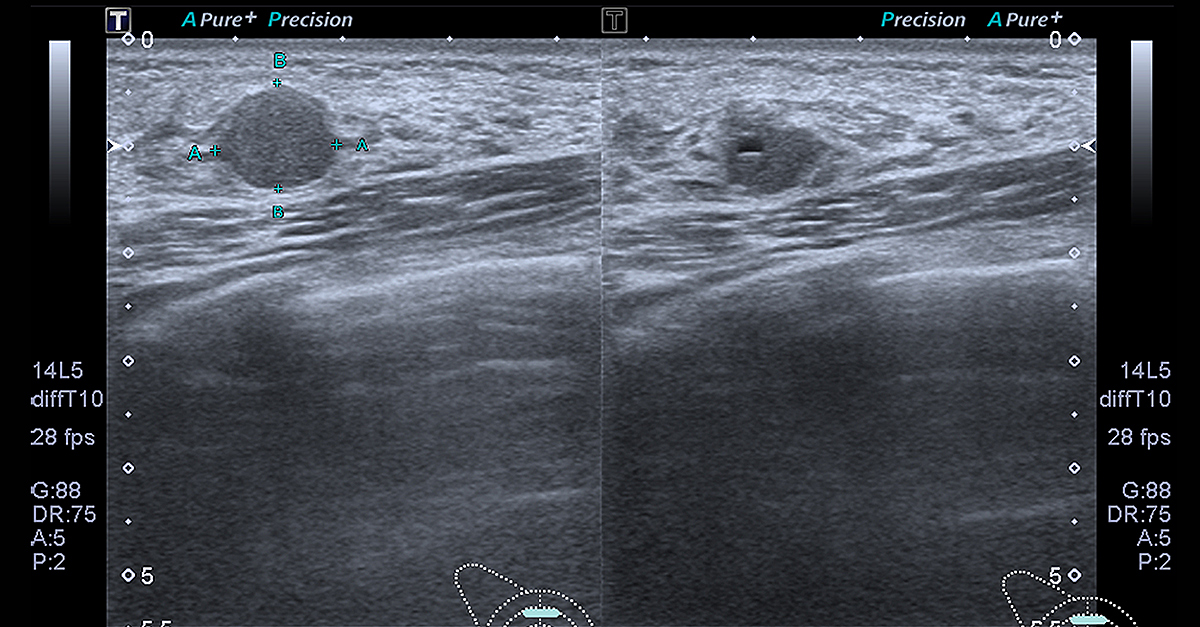

When you go in for a breast examination to determine whether a lump is benign or cancerous, your doctor will likely perform one or more tests, including a mammogram, an ultrasound or a biopsy, according to the American Cancer Society.

These tests will allow your doctor to determine whether the lump in your breast resembles breast cancer. A breast ultrasound may be performed if you have dense breast tissue or if your doctor needs additional images to analyze the growth following a mammogram. In some cases, a biopsy may be necessary. During a biopsy, the doctor will use a fine needle to extract tissue samples from any lumps in the breast and send them to the lab for further analysis.